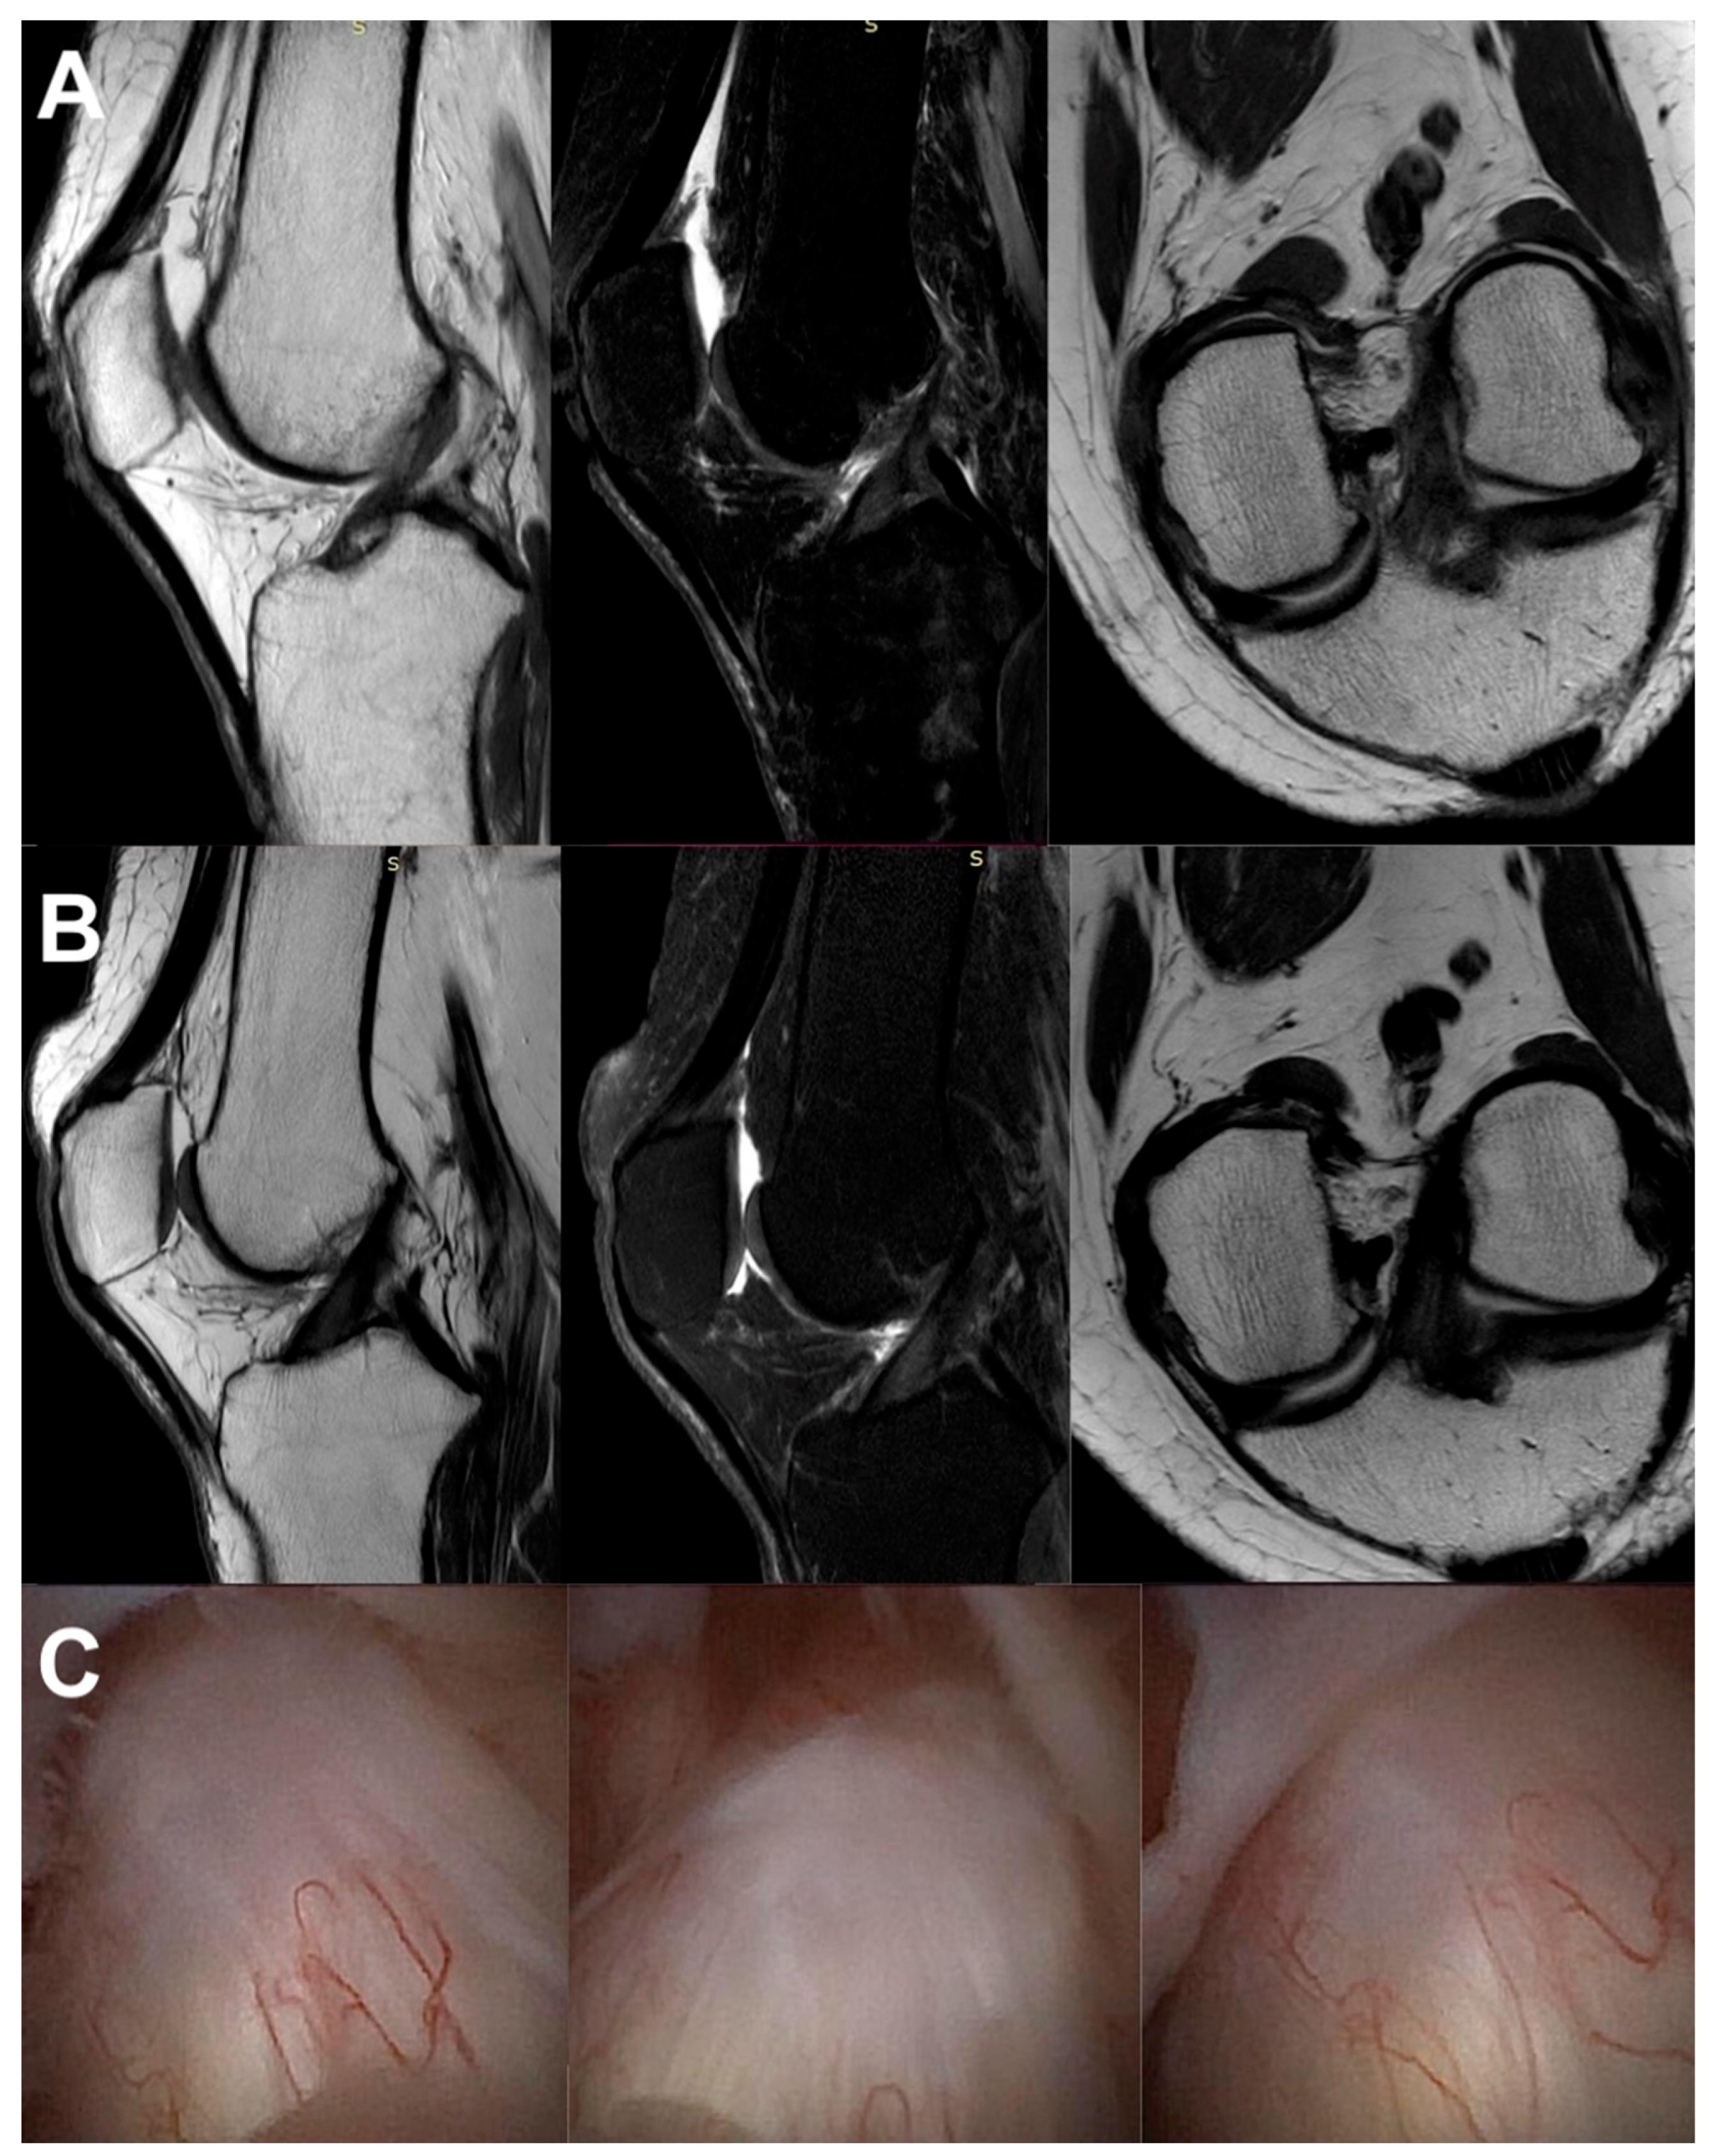

Figure 8.

The same knee MRI scans of a patient with an anterior cruciate ligament tear before treatment (A) and corresponding MRI scans after nanosurgery treatment with an RP-hCM injection (B). A nanoscopic view of the normal, healed ACL (C).